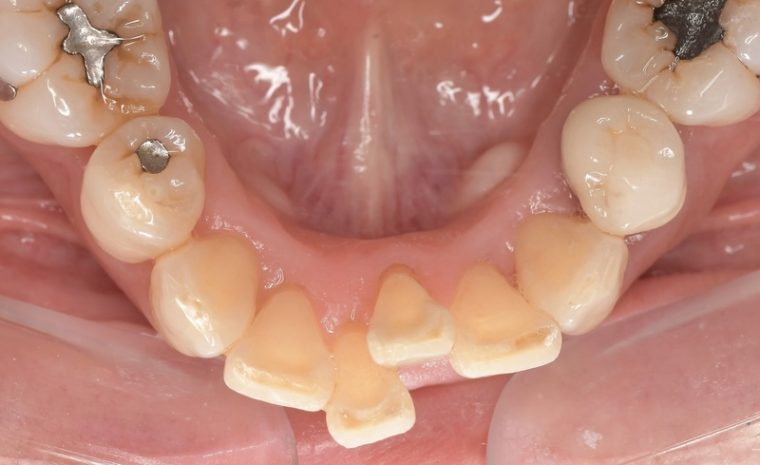

CASE 10

| 年齢・性別 | 38歳・男性 |

|---|---|

| 主訴 | 下顎 歯石除去したい |

| 治療内容 | スケーリング |

| 治療期間 | 30分 |

| 治療費 | 約1,500円(保険診療) |

| リスク・副作用 | 知覚過敏、歯肉退縮 |

| 治療方針 | 歯肉縁上歯石を除去してから歯肉縁下歯石を除去します。ご自身でのプラークコントロールができるようになったら定期検診に移行します。 |

| 担当者所見 | 半年ぶりの歯科医院の受診。歯石が付きやすいためセルフケアの重要性をお伝えして、定期的にクリーニングを行います。出血率が高く炎症が強いため、今後はセルフケアを強化して歯周病治療を行います。 |